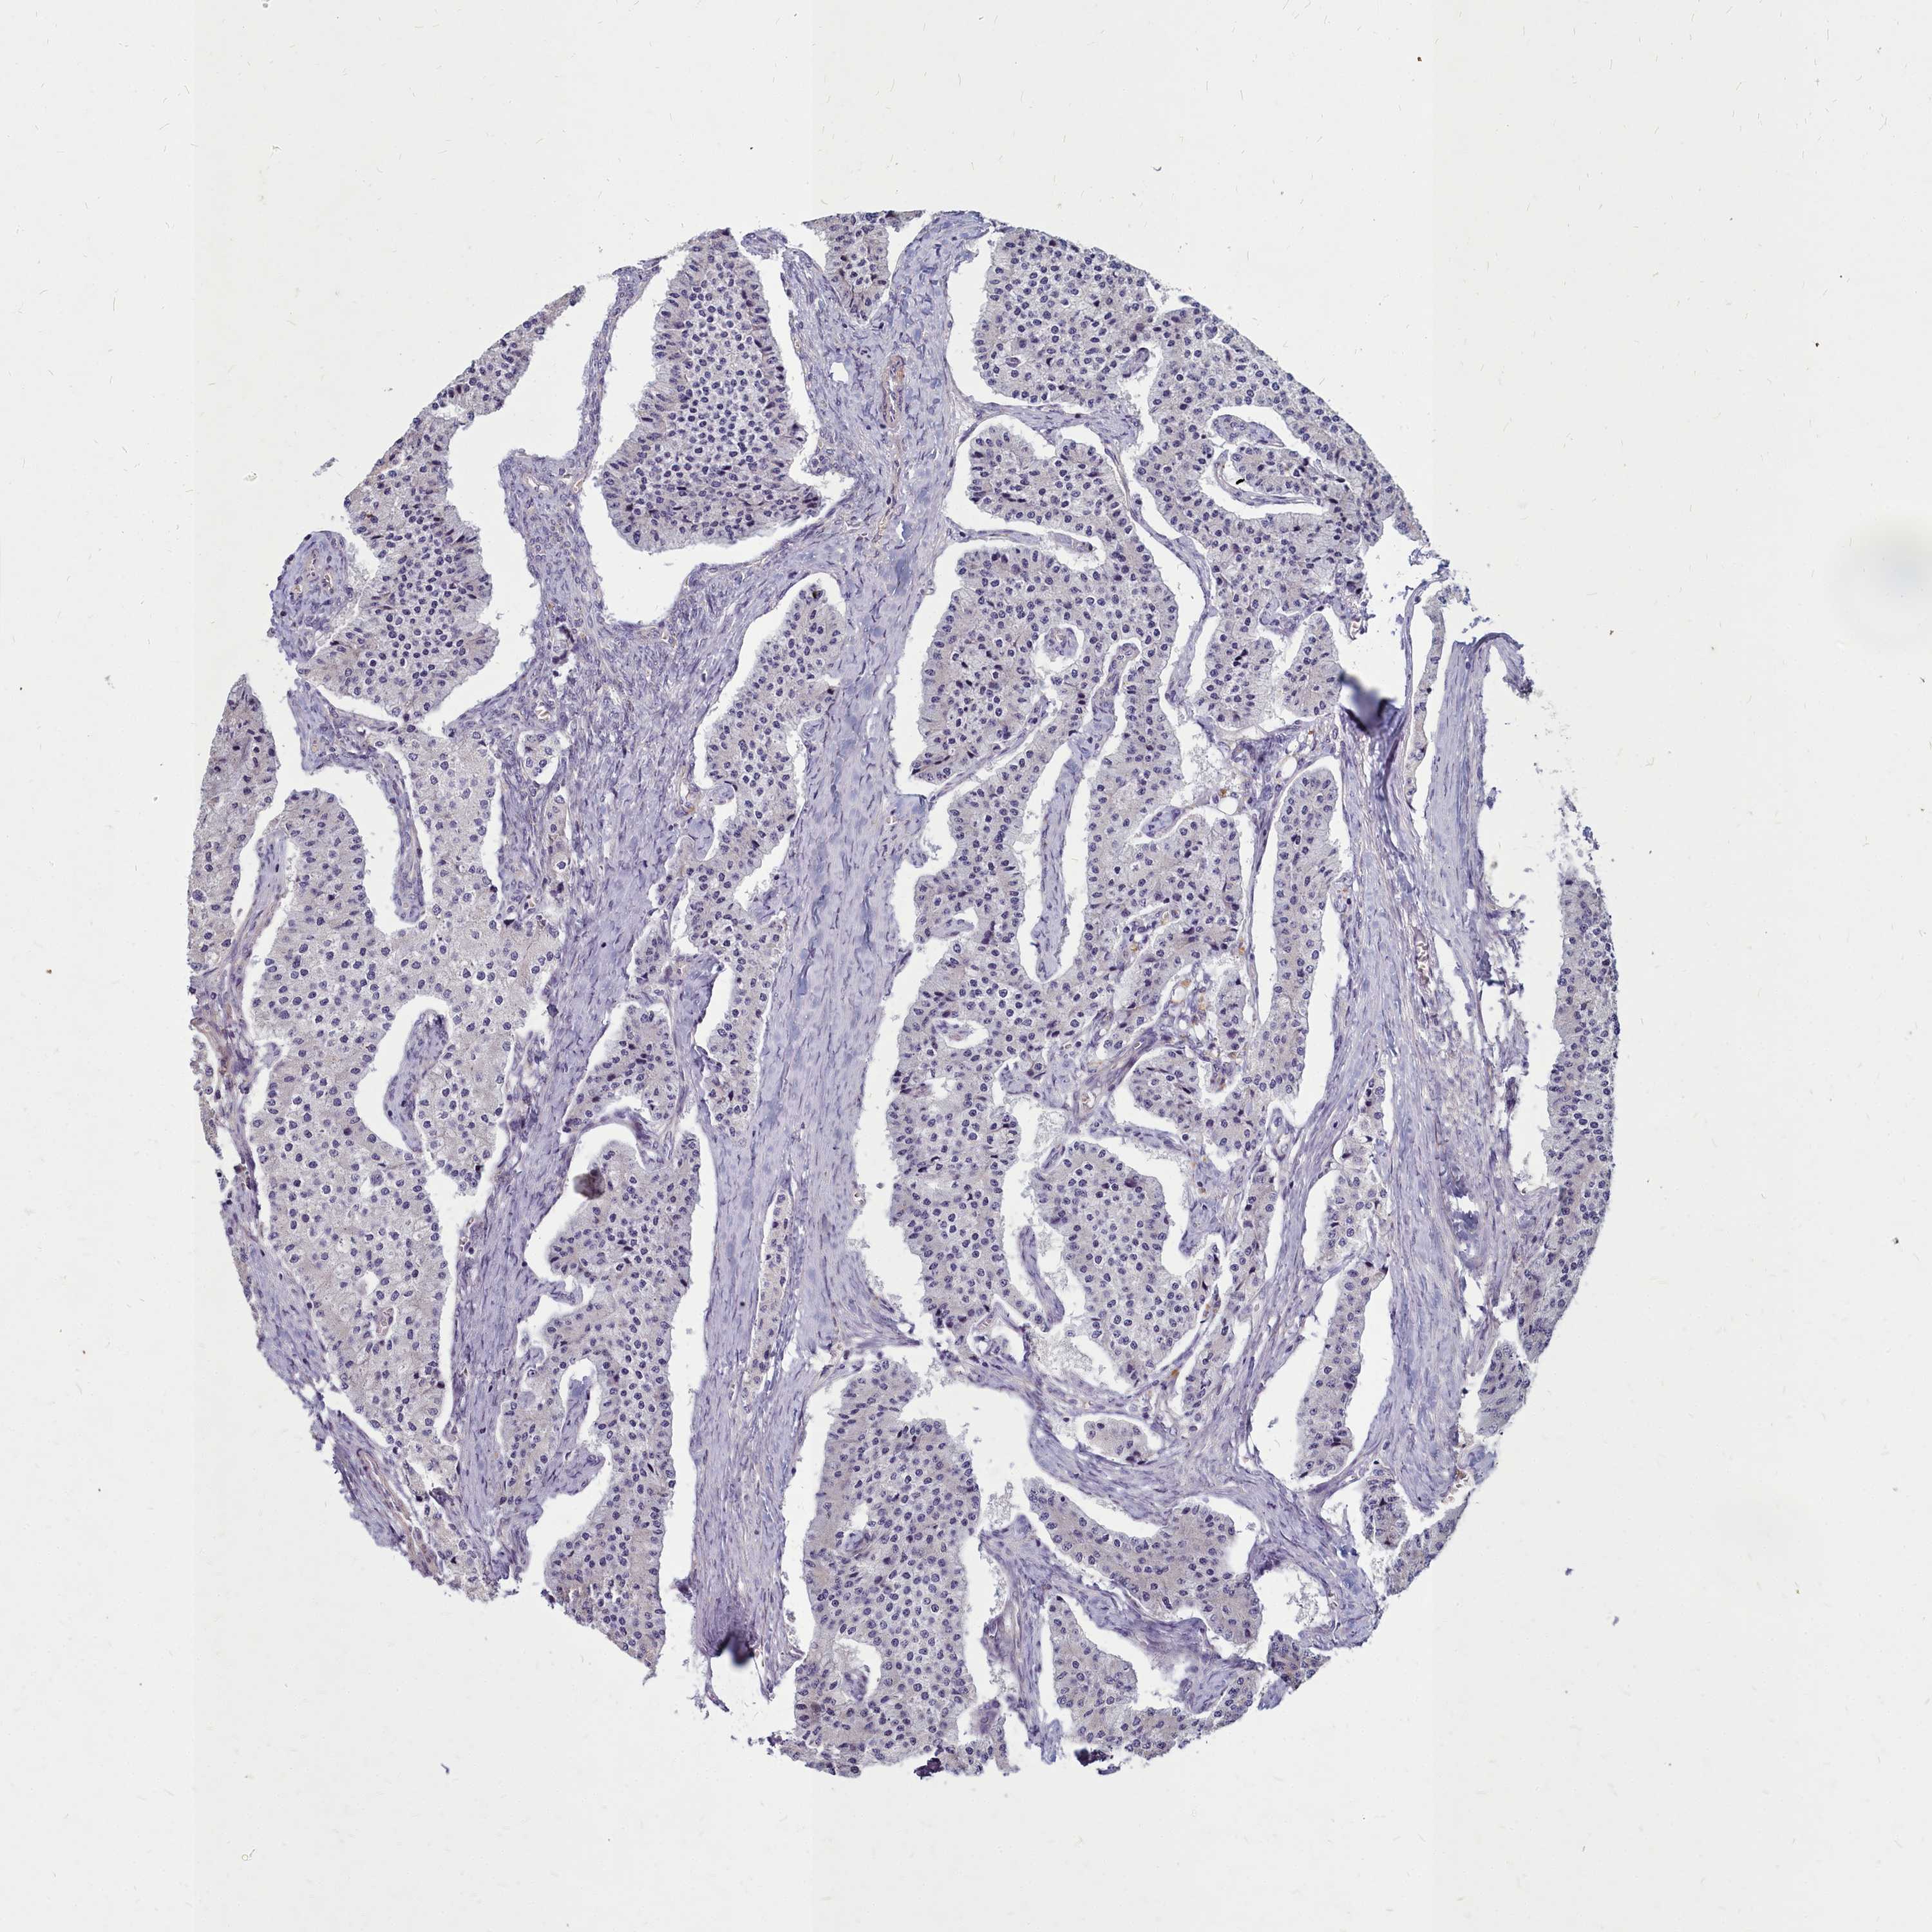

Neuroendocrine tumors

Human pathology

Carcinoid